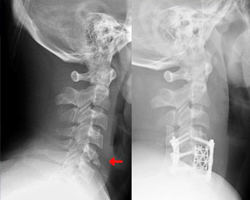

Spinal Fusion.

Spinal fusion is the most common surgery for back pain. In a spinal fusion, a surgeon joins spinal bones, called vertebrae, together. This restricts motion between the bones of the spine. Fusion also limits the stretching of nerves. Reduced spinal motion does not significantly limit activity for most people. One risk unique to spinal fusion surgery is incomplete fusion of the vertebrae. That can require additional surgery. While incomplete fusion is uncommon, smoking does increase the risk. Smoking also increases the risk of infection after back surgery.